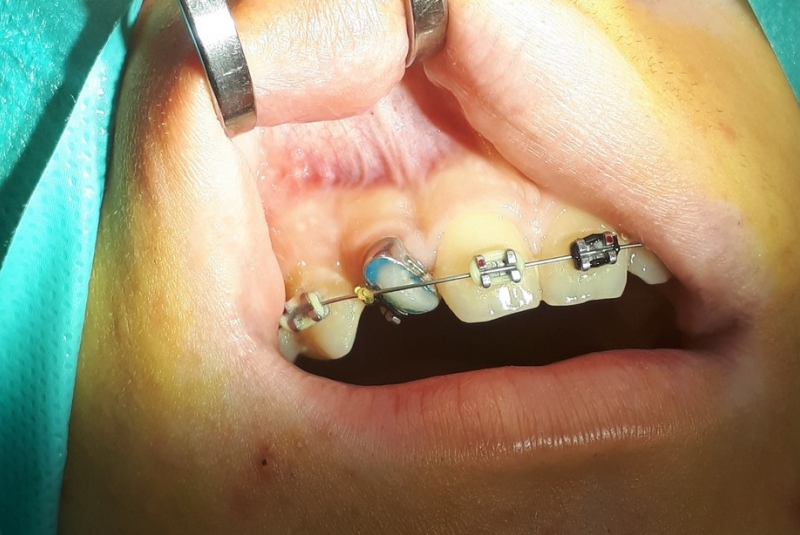

- Patefakcia (čeľustno-ortotodontické sťahovanie, zle postave- ných zubov do oblúka)